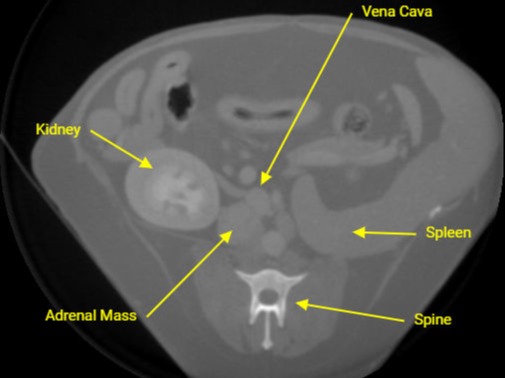

CT

Abdominal CT of Adrenal mass.